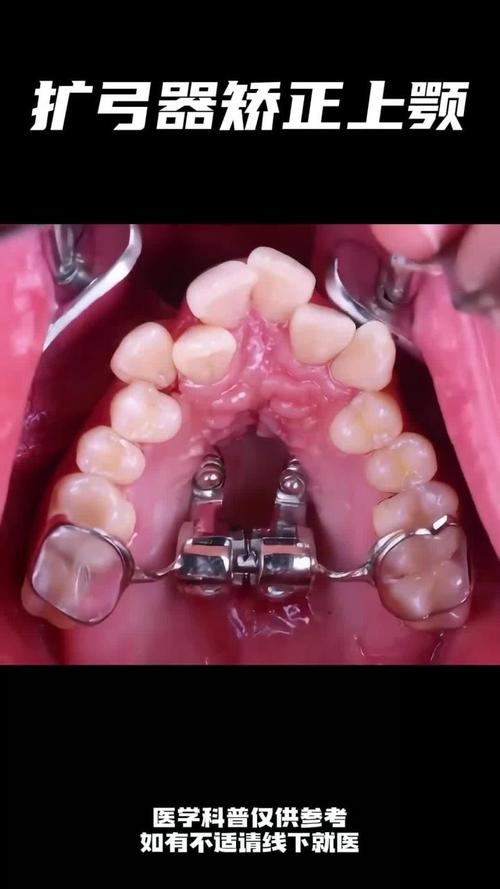

| 关闭拔牙间隙 | 4-6个月 | 通过滑动法或关闭曲法内收上颌前牙,同时使用支抗钉(植入上颌后牙区)防止后牙前移,确保间隙完全关闭。 |